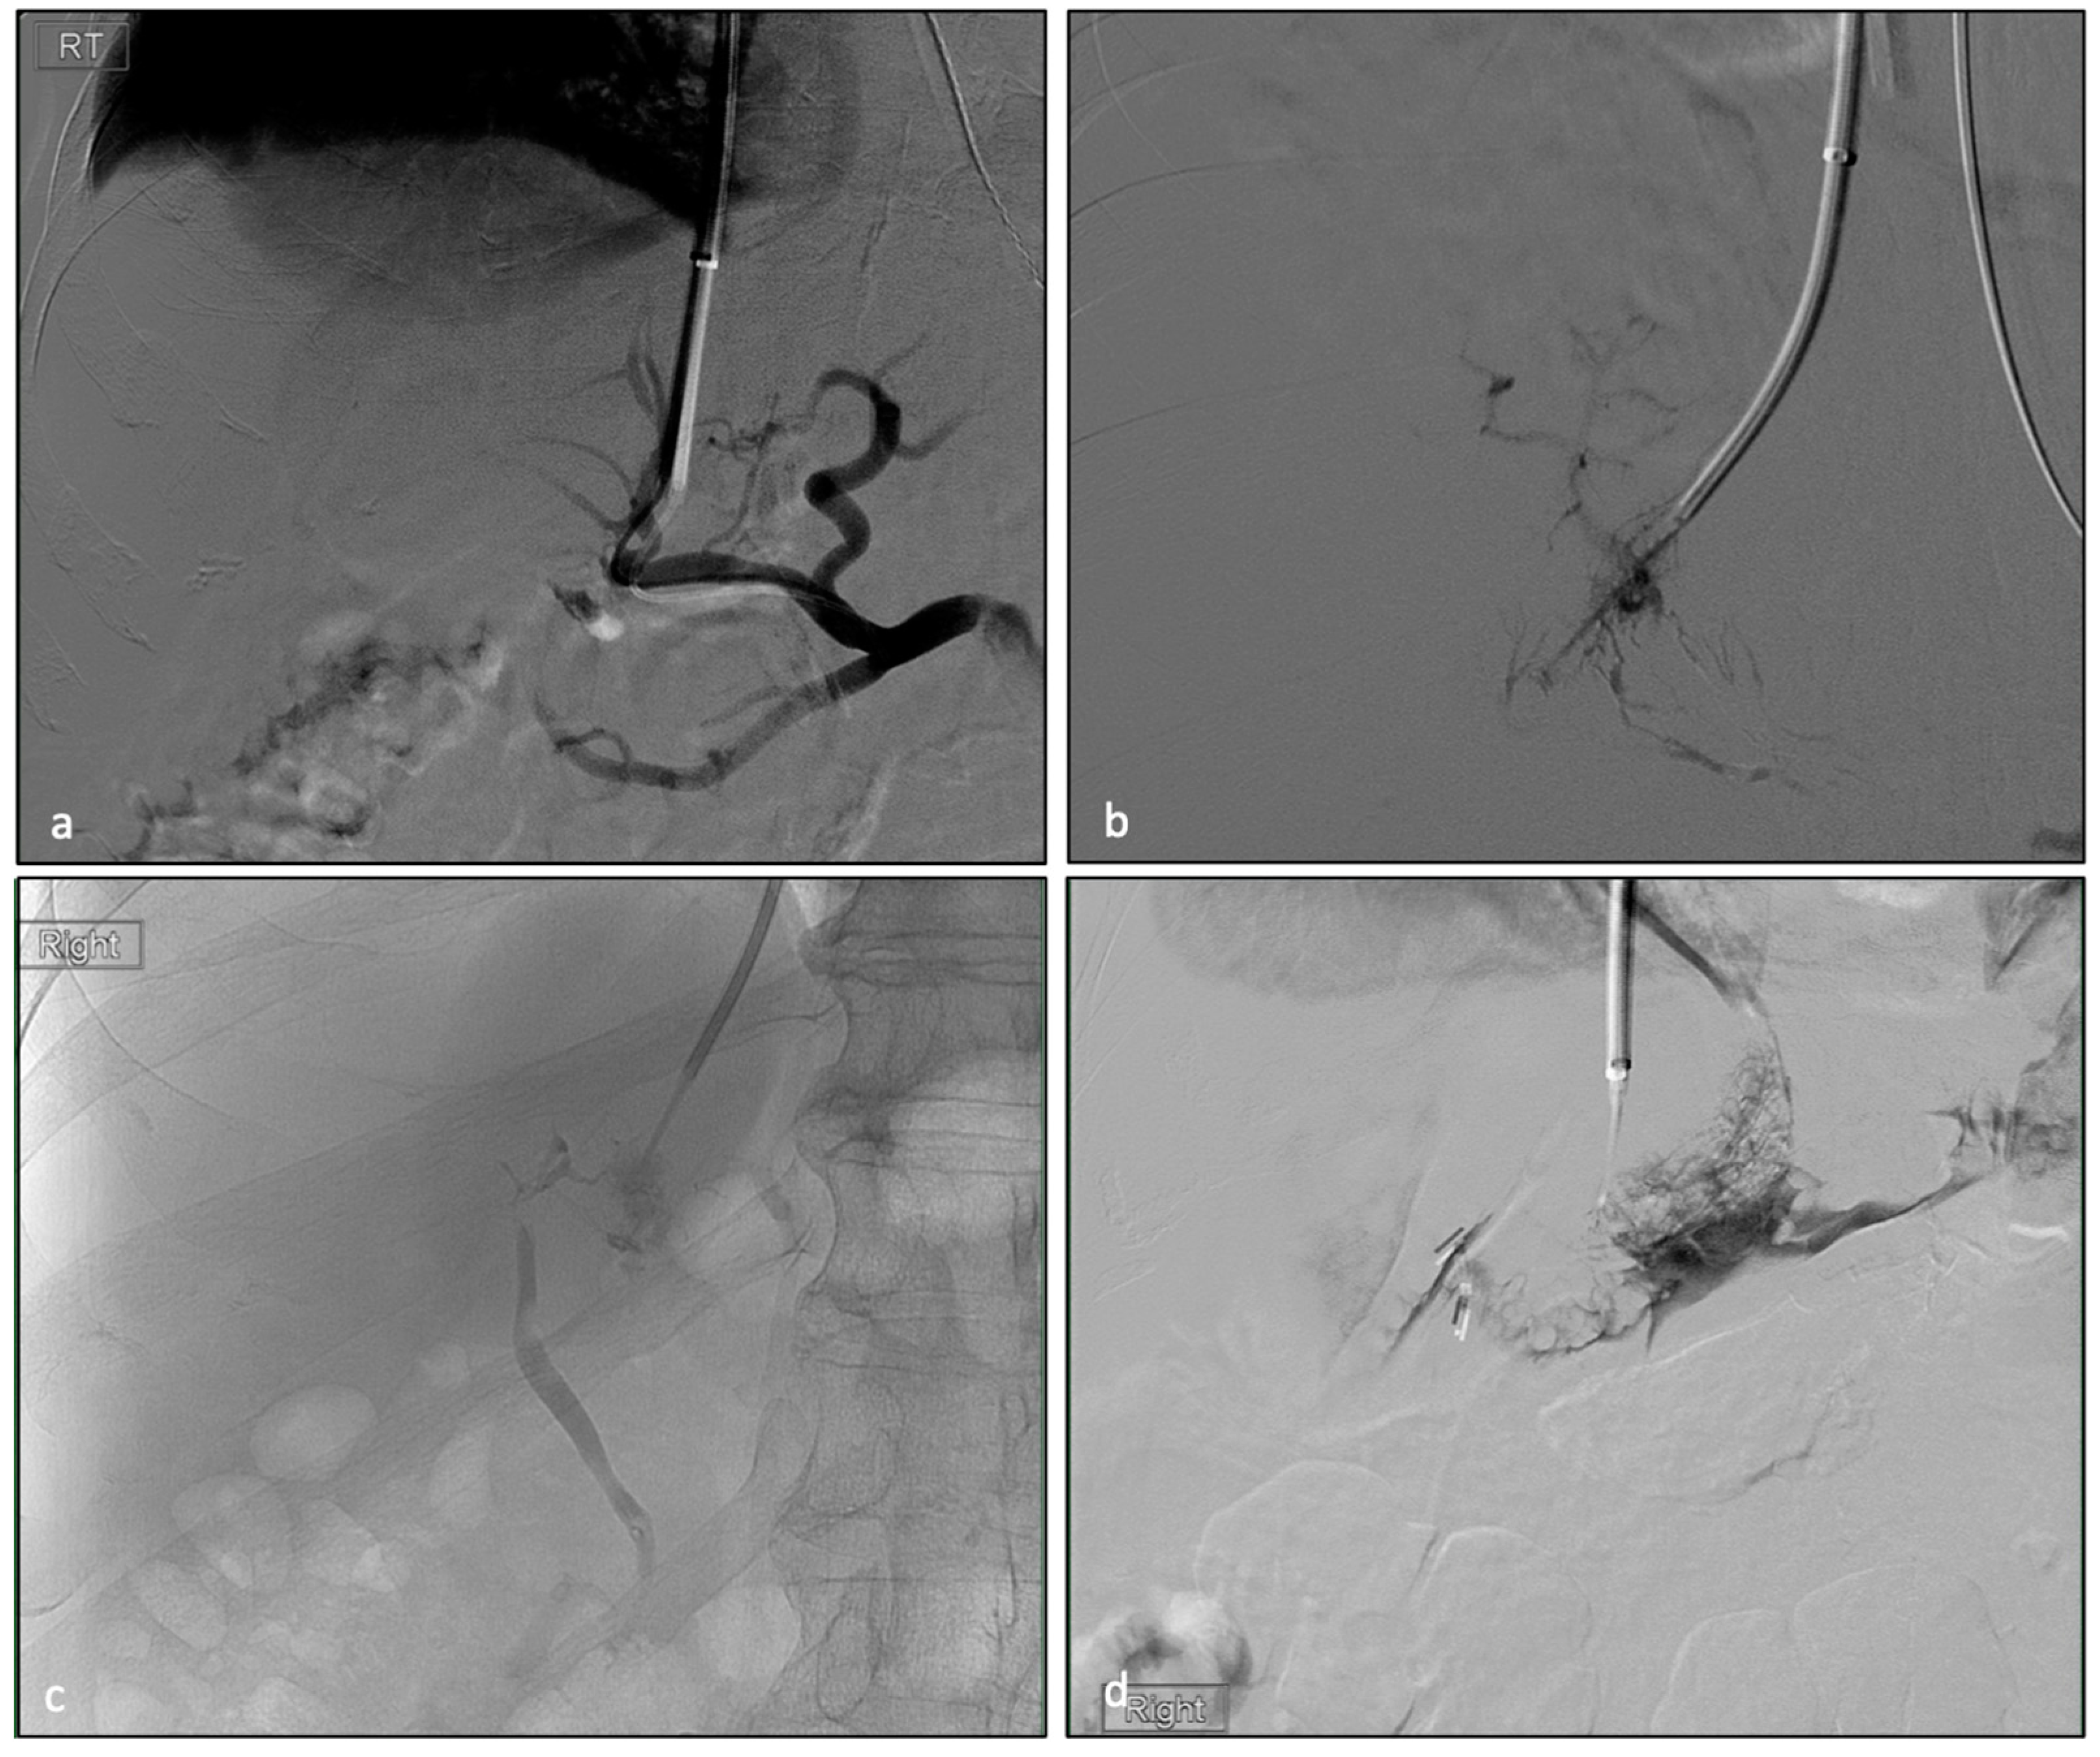

| NTP Type | Number of NTPs | % of Each NTP in Total NTPs |

|---|---|---|

| Biliary punctures | 28 (7.6%) | 34% |

| Extra-capsular punctures | 16 (4.3%) | 20% |

| Lymphatic punctures | 15 (4.1%) | 18% |

| Hepatic artery punctures | 12 (3.3%) | 15% |

| Combination of any NTP | 11 (3.0%) | 13% |

| ID | Biliary Puncture | Hepatic Artery Puncture | Lymphatic Puncture | Capsular Puncture | Clavien-Dindo Grading Complication in 30 Days | Complications | LOS (Days) |

|---|---|---|---|---|---|---|---|

| 6 | X | 0 | 0 | 0 | 1 | Focal segment 7 biliary ductal dilatation | 6 |

| 8 | X | 0 | 0 | X | 4B | Multiorgan failure | 56 |

| 30 | 0 | X | 0 | 0 | 2 | Hemoperitoneum need, blood transfuse | 13 |

| 35 | 0 | X | 0 | X | 2 | Hemoperitoneum need, blood transfuse | 2 |

| 41 | 0 | 0 | X | 0 | 1 | Mild hypotension | 2 |

| 43 | 0 | 0 | X | X | 5 | Hemoperitoneum, hypovolemic shock | 8 |

| 51 | X | X | X | X | 5 | Arteriobiliary fistula | 26 |

| 54 | 0 | 0 | 0 | X | 1 | Mild hypotension | 4 |